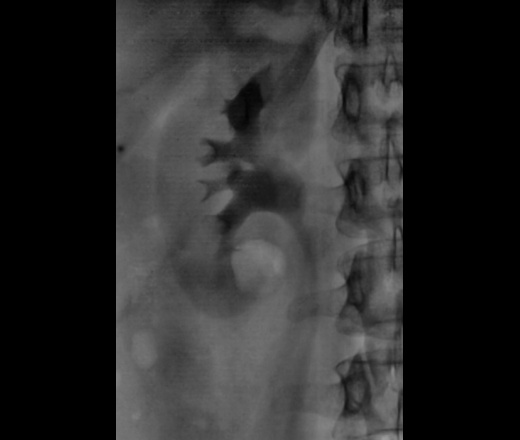

Классика жанра. Внутривенная урография.

Фрагменты рентгенограмм.

Неполная стриктура пиелоуретерального сегмента с престенотическим расширением лоханки с наличием "псоас-симптома".

Раз классика жанра, значит должно быть что-то известное. Но просто узнаваемого не вижу. Имеется субкомпенсированная стриктура лоханочно-мочеточникового сегмента правой почки с развитием гидрокаликоза и пиелоэктазии (гидронефрозом не назову, т.к. паренхима не истончена), да, с "+" псоас симптомом. Однако, постстенотическое расширение правого мочеточника, плавно теряющее контраст дистально, обусловлено гигантской миомой матки, сдавливающей мочеточник извне. Странно, как слева того же не произошло.